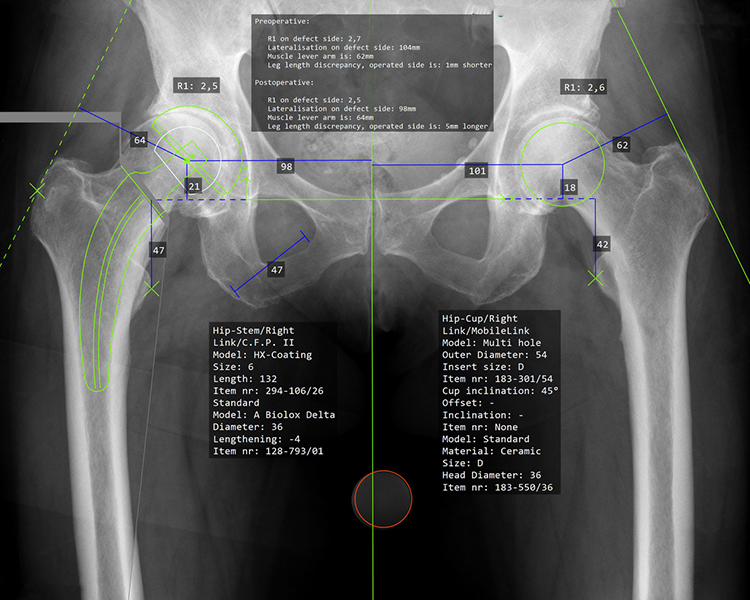

CAD-gestützte Planung

Nach meiner Überzeugung kann nicht jeder Patient mit einem einzigen Prothesenmodell erfolgreich versorgt werden. Daher arbeite ich seit vielen Jahren mit verschiedenen bewährten Prothesenmodellen, um nahezu jede individuelle Anatomie optimal abzubilden.

Nur durch diese maßgeschneiderte Auswahl können die Muskeln wieder in ihrer natürlichen Funktion arbeiten,  die Voraussetzung für schmerzfreies Gehen und bestmögliche Lebensqualität.

Die computergestützte (CAD) Planung ermöglicht es, jeden Eingriff präzise zu simulieren und die optimale Prothese für Ihre individuelle Anatomie auszuwählen, für maximale Präzision und langfristig erfolgreiche Ergebnisse.

computergestützte OP-Planung für optimale Ergebnisse:

• Patientenspezifische Anatomieanalyse

• Präzise Implantatauswahl & -positionierung

• Simulation von Offset, Beinlänge & Gelenkzentrum

• Biomechanisch optimierte Rekonstruktion